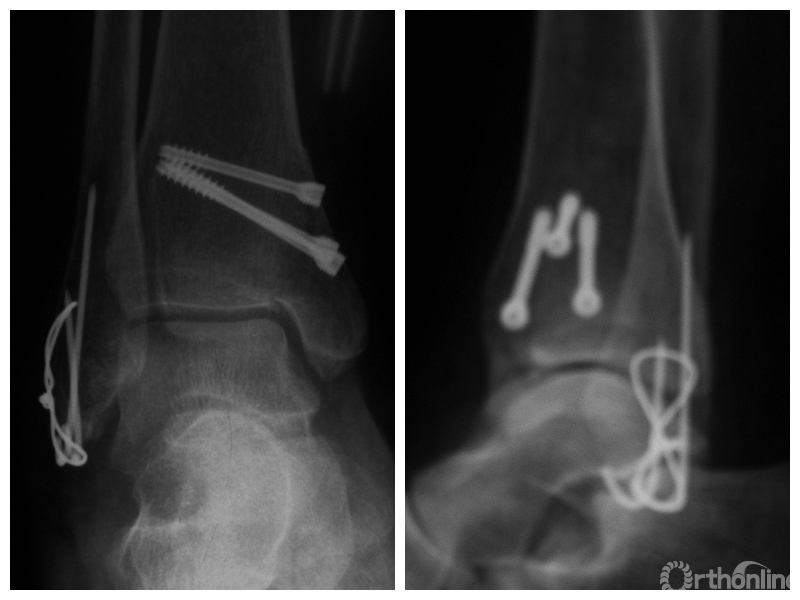

图1 支撑钢板固定组患者,女,63岁,右侧旋后-内收型II度踝关节骨折 a. 术前正侧位X线片;b. 术前CT;c. 术后2周正侧位X线片;d. 术后2年正侧位X线片

图1c 术后2周正侧位X线片

图2 螺钉固定组患者,女,37岁,左侧旋后-内收型II度踝关节骨折 a. 术前正侧位X线片;b. 术前CT;c. 术后2周正侧位X线片;d. 术后1年正侧位X线片

图2c 术后2周正侧位X线片